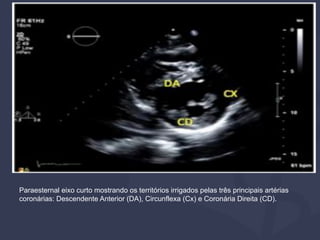

PARAESTERNAL EIXO CURTO

Paraesternal eixo curto mostrando os territórios irrigados pelas três principais artérias

coronárias: Descendente Anterior (DA), Circunflexa (Cx) e Coronária Direita (CD).